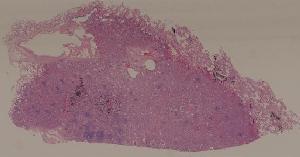

57. Carcinoma of the lung